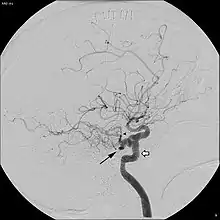

Angiogram demonstrating persistent trigeminal artery, as indicated by the black arrow.